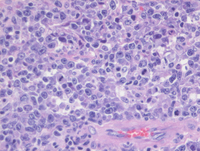

H&E images of histology of PCNSL

The specimen consists of neural tissue with a diffuse lymphoid proliferation (1a) which is composed of medium to large sized lymphoid cells (1b) which have intermingled apoptotic bodies, reactive small lymphocytes and macrophages and show perivascular accumulation (1c). On higher power the lymphoid cells are noted to be pleomorphic with increased cytoplasm and prominent centrally located single nucleoli, consistent with immunoblasts and numerous mitotic figures in the background (1d).